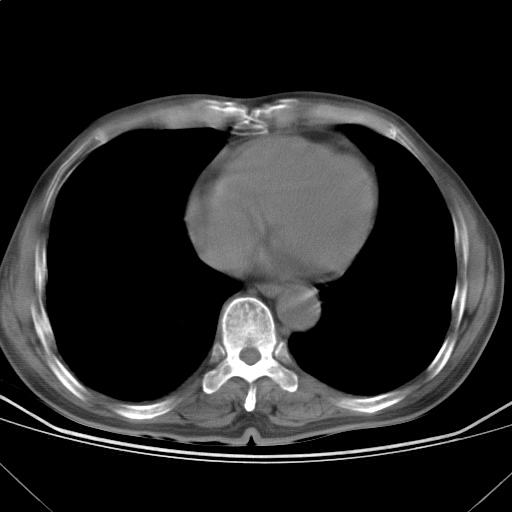

以下是引用随光逐影在2009-5-1 13:53:00的发言:[br]考虑为:1)两肺血行播散型肺结核;2)右肺下叶炎症感染。3)右侧胸膜增厚。